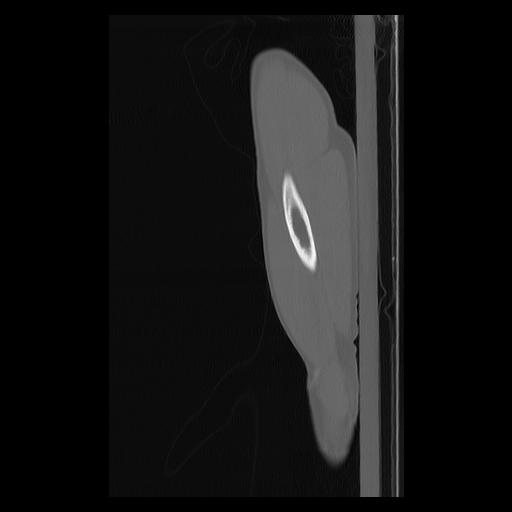

33 PULMON,CE,Sagittal,3.000,PULMON,Sagittal,